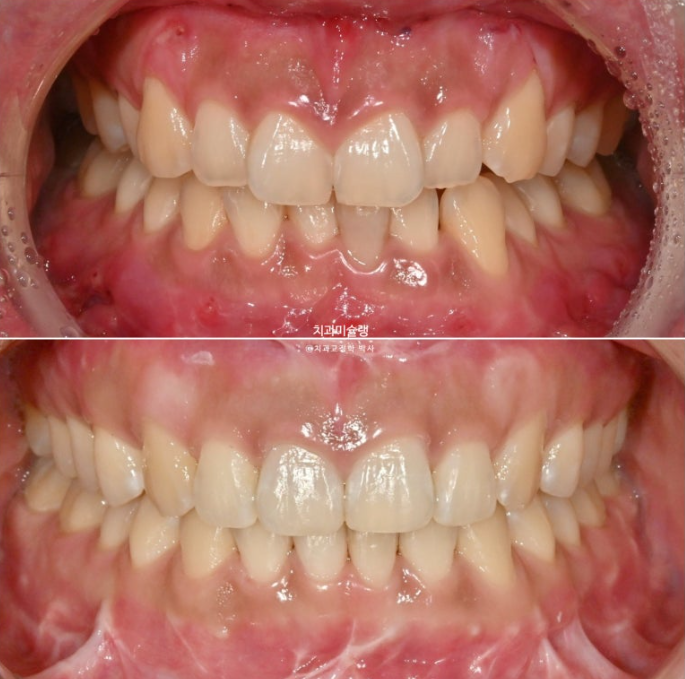

선수술 후 한달간의 회복기를 거쳐 25년 1월 본원에 내원했을 때의 교합 상태입니다.

25.01

아래 앞니 하나에 변색이 보입니다.

앞니 두 개는 나비치아 돌출이며

어금니 교합이 떠있습니다.

앞니에 배열이 삐뚤합니다.

이 정도의 상태라면 14개 장치 안에서 해결이 가능합니다.

즉 인비절라인 라이트로도 충분합니다.

25년 6월 14개 장치를 모두 낀 후 모습입니다.

25.06

수술 직후 변색이 되었던 아래 앞니는 신경이 돌아오며 정상 색깔을 회복중입니다.

교합은 좋은편이며

배열도 거의 완성이 되었습니다.

25.02~25.10